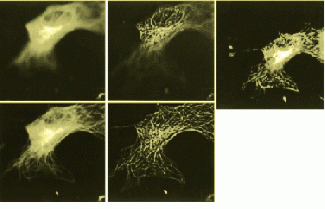

FIGURE 1. Five images of a cell show optical slices as raw images (upper and lower left) and as deconvolved images (upper and lower middle). Reconstitued image (above) shows a rendering of 40 optical slices from the cell. (Images courtesy Jie Chen, Melvin L. Griem and Peter F. Davies of the University of Chicago).

Each image of a 2-D section of a cell includes unwanted information from neighboring sections, resulting in a blurred image. Thus, the 2-D images must be deblurred. The system uses a measured point-spread function (PSF) for deblurring images. Because a measured PSF is used, most of the imperfections in the optics and most of the other nonideal characteristics of the system are accurately modeled. Measurement of the PSF requires acquisition of a set of 2-D images of a small fluorescent bead at the center of a neutral specimen slide. The acquisition procedure uses the identical procedure as that used to image cells. The result is the PSF, a set of 2-D images that represent the response of the microscope to a point object (the bead) at each of the optical planes used in the cell imaging sequence. The PSF is used with a nearest-neighbor algorithm to sharpen (deblur) cell images before they are reconstructed in three dimensions.

The nearest-neighbor deblurring algorithm used in the system is based on the assumption that blurring of image slices is caused by light scattering only from the slices directly above and below a specific slice. Because the algorithm requires limited data, deblurring of 2-D images on the IBM SP-2 computer can begin as soon as three slices of data have been acquired and transferred from the university to Argonne Laboratory. Thus, imaging and deblurring can occur simultaneously. As the deblurring of multiple slices can be distributed, deblurring of several slices proceeds simultaneously on the multiple nodes of the SP-2. Construction (stacking) of a 3-D image from the deblurred 2-D image occurs when all the slices have been deblurred.